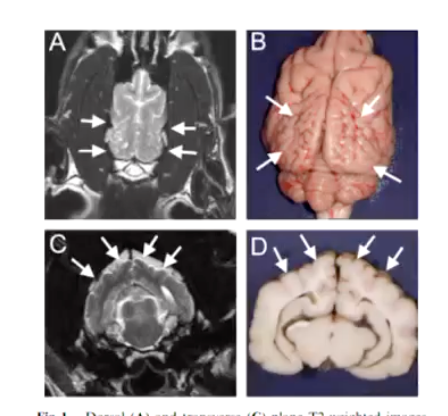

The abnormality is characterized by agenesis of all derivatives of the medial nasal prominence; lateral duplication of most derivatives of the maxillary process; including the canine teeth and whiskers fields; telencephalic meningoencephalocele; and secondary ocular degeneration (Fig. 1c and d)

Genes associated with Burmese Cats due to trying to make faces flatter